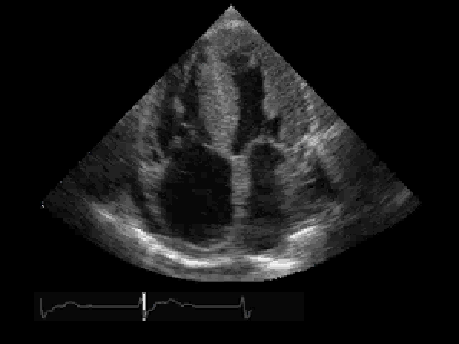

I was set up to have a stress echo-cardiogram. I had to have lots of little sticky things places all over my chest. The technician got me ready. I made my way to the tread mill. They wanted to get my heart rate up to 135. By the time it reached 86, I was panting and hurting. I felt like the only runner in a race that was held last week. I hurried back to the table and the technician ran the hand held device all over my chest. There’s your mitral valve. There’s your tricuspid valve.

I was looking at my own heart. I was watching it pulsate. She turned the sound on. It sounded like my mothers Maytag. But, I was watching my very own heart…beating and moving blood through my body…to keep me alive!

So, I had to find an image on the internet for you to see. It’s not me, but it looked something like me.

Not on the outside, but on the inside.

[Important Note: For any of my readers who are cardiologists, or who have recently purchased a copy of “Cardiology For Dummies” from Amazon, this is NOT my heart’s image. This is important to note because in this image is a very serious heart defect. I do not have such a defect. My only problem is my main circulatory organ breaks easily…so, with me and with all those you love…HANDLE WITH CARE]